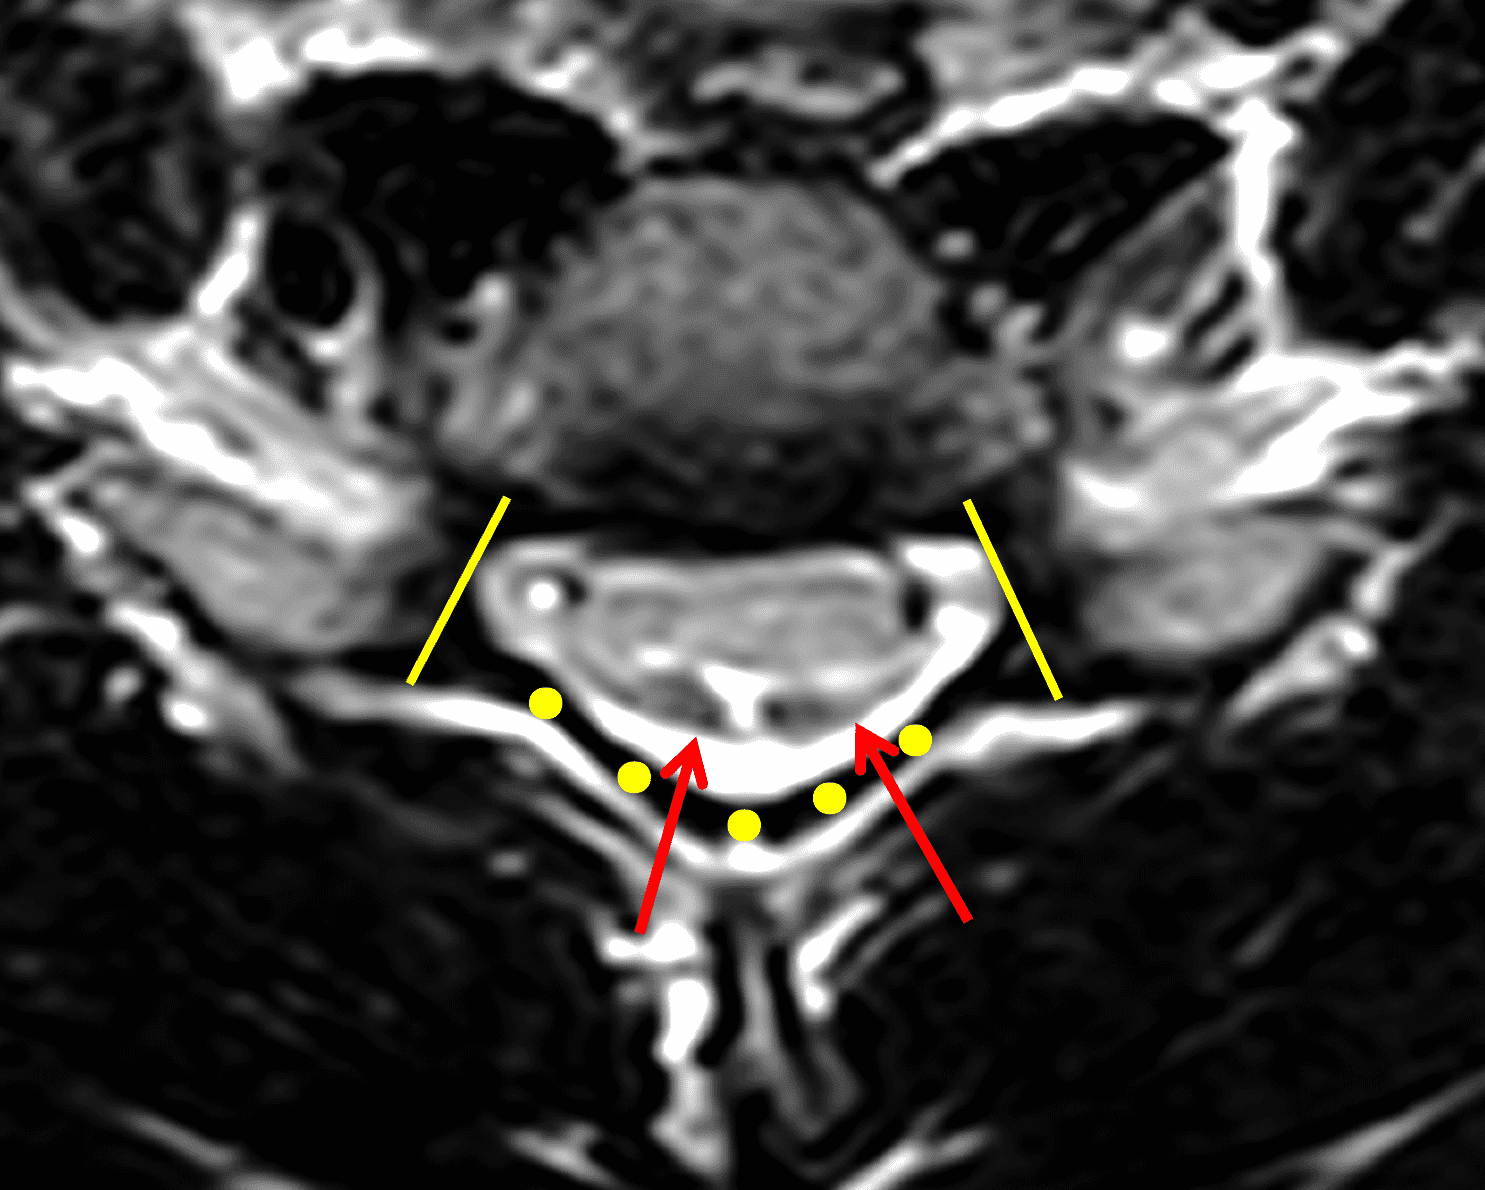

The LOA sign was proposed as a finding suggesting HD on neutral position MRI of the cervical spine.29 The degree of loss of attachment of the posterior dural sac and subjacent lamina are evaluated on each side of the lamina at C4 to C6 levels on axial T2-weighted images, with separation along more than one-third of the lamina on one or both sides considered positive for LOA. To assess the degree of LOA, the lamina is defined medially by the point of junction of the lamina and laterally by a tangential line along the medial aspect of the pedicle and then divided into three equal parts (Figure 6). The LOA sign was found to have a sensitivity of 93.5% and specificity of 98% for HD. The LOA sign was investigated in the first multisite North American study by Lehman et al.5 and found to have a lower sensitivity of 70% but similar specificity of 100%. The authors confirmed that the LOA sign and other findings are often present on neutral position MRI and in the appropriate clinical scenario, should raise suspicion and prompt further assessment by flexion MRI to confirm the diagnosis.

Figure 6: Axial images demonstrating the loss of attachment (LOA) sign. (6A) T2-weighted and (6B) T1-weighted images in a normal spine (same patient as Figure 3). Yellow lines mark the lateral extent of the laminae, which have been divided into thirds (yellow dots). The posterior dura (red arrows) is firmly attached to the lamina. (6C) T2-weighted and (6D) T1-weighted images of a spine with HD (same patient as Figure 1) show the lamina divided into three equal parts (yellow lines and dots) and displacement of the posterior dural sac, right greater than left, with loss of attachment (red arrows). The separation involves more than one-third of the length of the lamina on both sides.